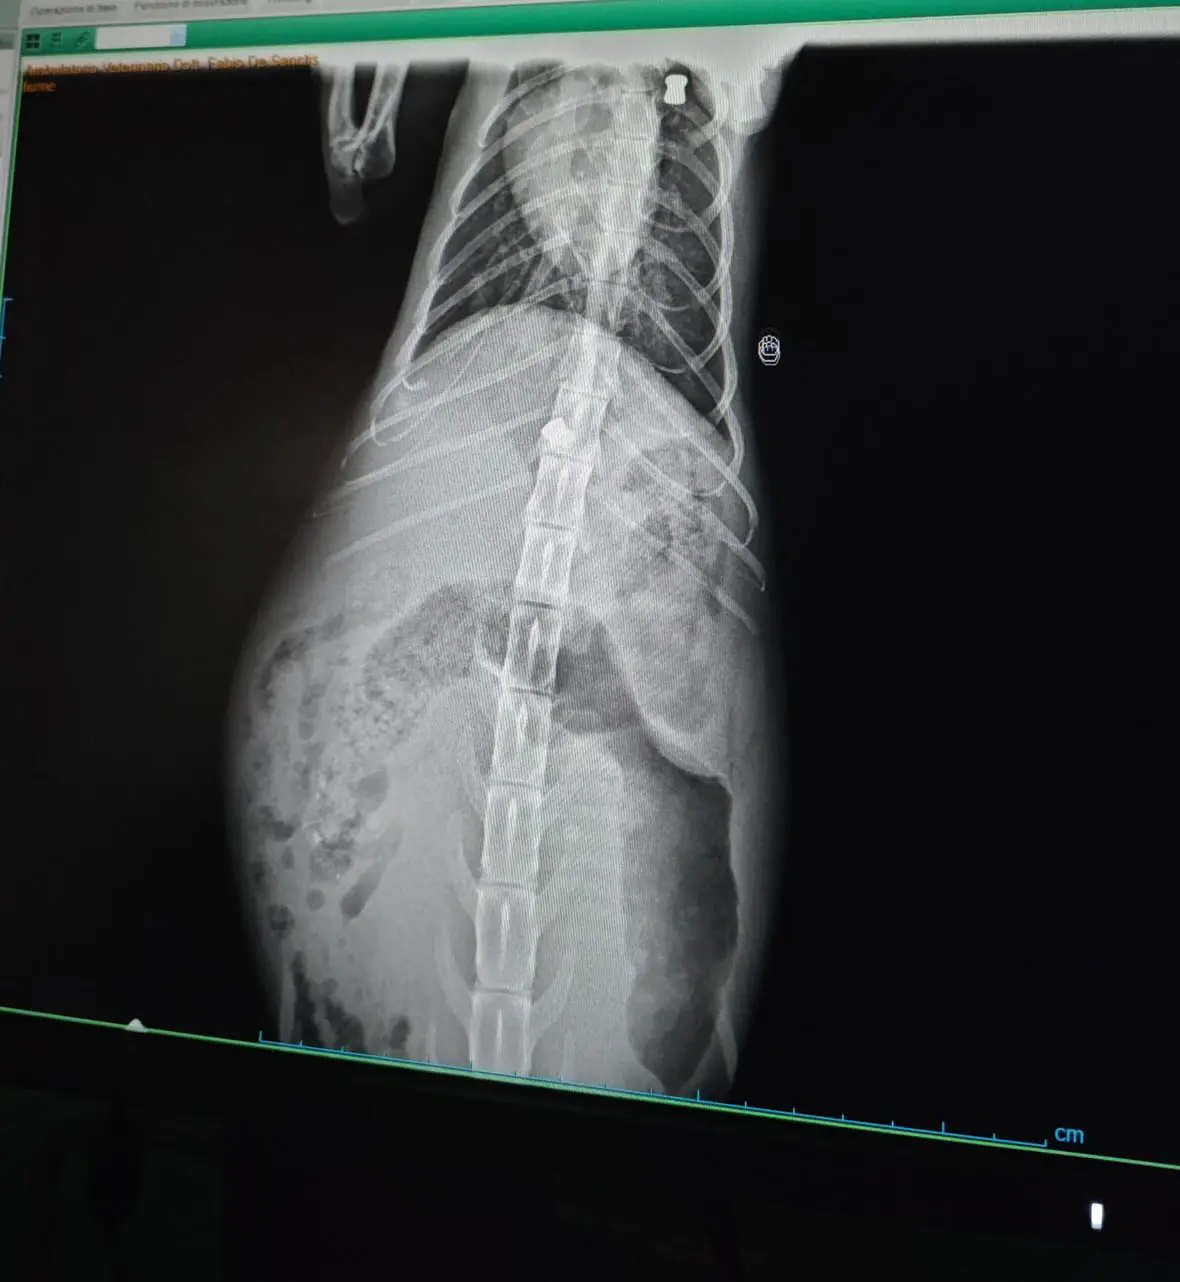

Sotto la pioggia dei giorni scorsi, la piccola è stata portata dal veterinario per una prima visita, dove la radiografia ha rivelato una scoperta terribile: nel suo corpo sono stati trovati due pallini di piombo, uno conficcato nella colonna vertebrale e un altro vicino al cuore.

Secondo il veterinario, non ci sono dubbi: la gattina è stata colpita da qualcuno con un’arma ad aria compressa o da fuoco, ed è quindi vittima di un gesto crudele e ingiustificabile. Ora è purtroppo paralizzata e necessita di cure specialistiche per valutare se sia possibile intervenire chirurgicamente e restituirle la vita dignitosa che merita.